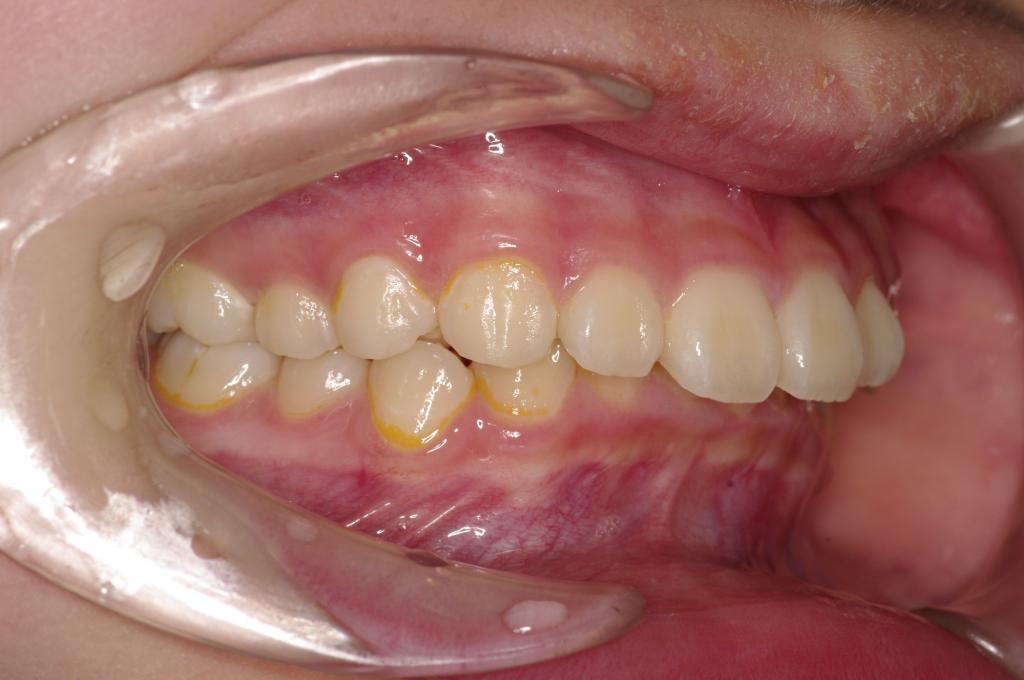

前歯、出っ歯・開咬の矯正治療

(治療期間、治療前後写真、治療方法、費用)WORKS